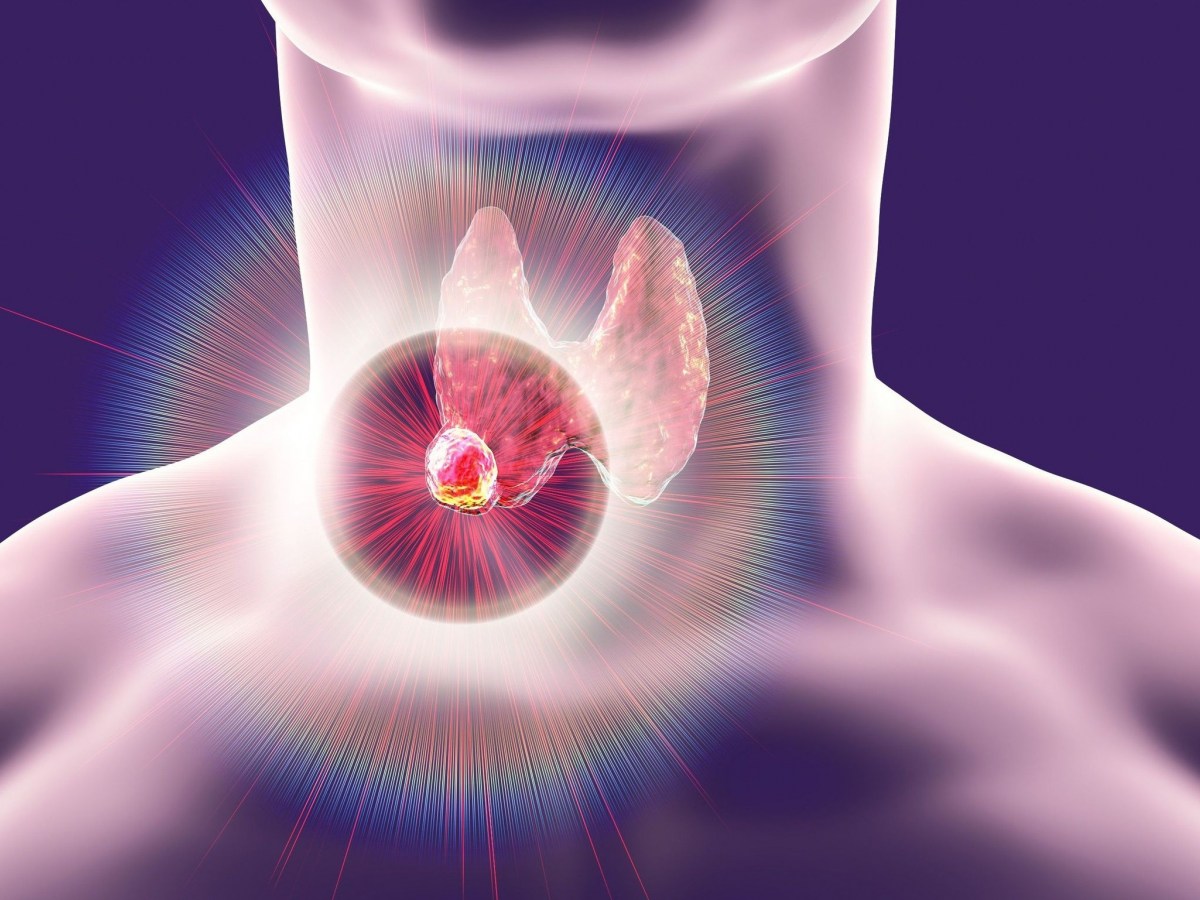

Μια νέα μελέτη, διαπίστωσε πως τα «παντοτινά χημικά» που υπάρχουν σε όλα τα σπίτια, μπορεί να αυξάνουν τον κίνδυνο καρκίνου του θυρεοειδούς.

Οι ερευνητές διαπίστωσαν ότι οι ασθενείς με καρκίνο του θυρεοειδούς είχαν πολύ περισσότερες πιθανότητες να φέρουν παντοτινά χημικά στον οργανισμό τους.

Οι ερευνητές πήραν δείγματα αίματος από 88 πάσχοντες με καρκίνο του θυρεοειδούς και από 88 υγιείς συνομηλίκους τους, αντίστοιχου σωματικού βάρους, φύλου, φυλής κλπ.

Η μέση ηλικία των εθελοντών ήταν τα 46 χρόνια. Οι ερευνητές στο Νοσοκομείο Mount Sinai της Νέας Υόρκης, εξέτασαν στα δείγματα αίματος οκτώ παντοτινά χημικά.

Οι μετρήσεις έδειξαν πως όσοι εθελοντές είχαν εκτεθεί σε ένα είδος PFAS που λέγεται n-PFOS (υπερφθορο-οκτανοσουλφονικό οξύ) είχαν 56% περισσότερες πιθανότητες να πάσχουν από καρκίνο του θυρεοειδούς.

Το εύρημα επιβεβαιώθηκε σε περαιτέρω αναλύσεις σε υποομάδα 31 ασθενών που είχαν διαγνωστεί με τη νόσο εντός του τελευταίου έτους πριν ενταχθούν στη μελέτη.

Οι ερευνητές βρήκαν επίσης θετική συσχέτιση του καρκίνου του θυρεοειδούς με παντοτινά χημικά, όπως το υπερφθορονονανοϊκό οξύ, το υπερφθοροοκτυλοφωσφονικό οξύ, το υπερφθοροεξανοσουλφονικό οξύ κ.α.

Τα ευρήματα «επιβεβαιώνουν ότι τα PFAS συνιστούν υγειονομική κρίση», δήλωσε η ερευνήτρια Lauren Petrick, αναπληρώτρια καθηγήτρια Περιβαλλοντικής Ιατρικής & Δημόσιας Υγείας στην Ιατρική Σχολή Icahn του Mount Sinai.

«Σήμερα είναι σχεδόν αδύνατον να αποφύγει κάποιος τα PFAS στις καθημερινές δραστηριότητές του. Ελπίζουμε ότι τα νέα ευρήματα θα αυξήσουν την ενημέρωση για τη σοβαρότητα του προβλήματος και θα οδηγήσουν σε αλλαγές στη βιομηχανία που θα τα περιορίσουν» πρόσθεσε.

Τα ευρήματα δημοσιεύονται στην ιατρική επιθεώρηση eBioMedicine.